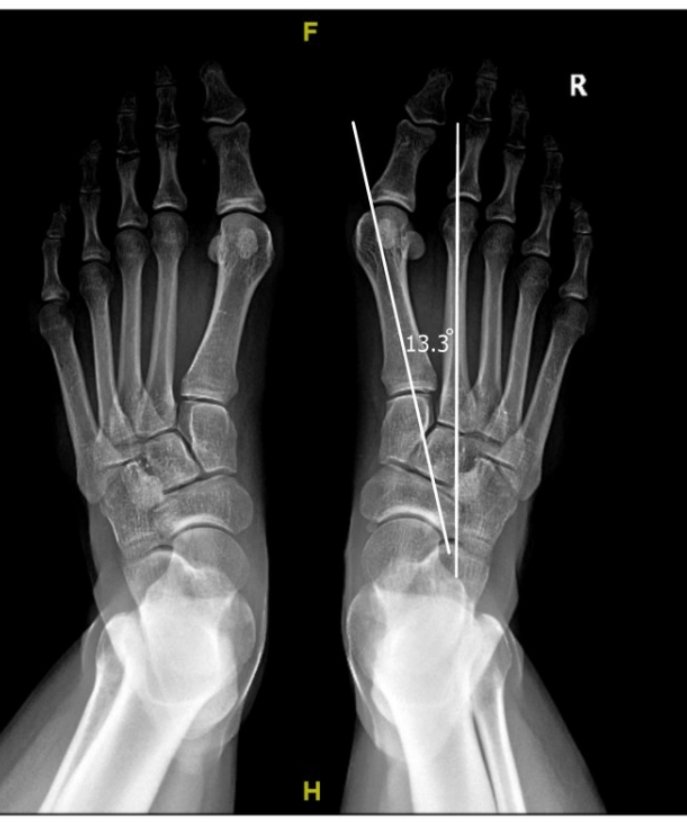

الأشعة:

- توضح درجة الانحراف

- انحراف بالمشط الاول للقدم

6️⃣العلاج الجراحي:

- يعتمد على درجة الانحراف و وجود مرونة في مفصل المشط الأول بالقدم

-الهدف من الجراحة هو إعادة استقامة المشط الاول و استقامة الأصبع الكبير